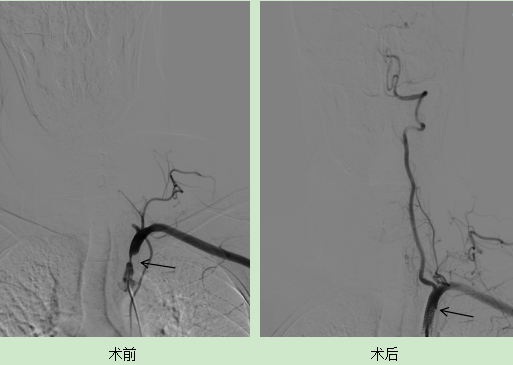

手术进行顺利,术后李大爷的左锁骨下动脉狭窄得到显著的改善,血管显影效果良好,双上肢血压基本一致,李大爷频繁发作的头晕症状基本上消失了。在术后的第三天,李大爷便康复出院,重新回归了正常的生活。 眩晕二科 沧州市中心医院神经内科医学中心眩晕二科是集医疗,预防,科研,教学全面发展的综合性病区,是一支经验丰富,技术精湛,业务素质强,学术梯队健全合理的专业技术队伍。医护人员共25人,其中副主任医师5人、主治医师4人、住院医师3人,均为国内知名高等医学院校研究生毕业,各级医师均完成了北京宣武医院,北京天坛医院,北大医院等知名医院的进修学习任务。 眩晕二科拥有国际先进眩晕诊疗设备,如眼震视图仪、视频头脉冲试验系统等,能够精准评估患者的前庭功能状态,对于常见的眩晕疾病,可以迅速诊断精准治疗,减少患者来往医院次数,节省费用。对于复杂疑难的眩晕疾病,眩晕二科拥有整套成熟的诊疗机制,还可通过医院多学科会诊、北京各大医院专家会诊指导,依据患者病情,制定个性化治疗方案及康复计划,并提供专业的康复指导,通过前庭康复训练等手段,帮助患者恢复前庭功能,提高生活质量。 科室诊疗范围: 科室特色技术项目: 1、目前在眩晕诊治方面有着鲜明的特色和传统优势,科室内医务人员先后于北京天坛医院眩晕中心,北京航天中心医院师从国内眩晕大咖对眩晕疾病的诊疗达到国际水平,同时本科室配备眼震电图,视频脉冲甩头等先进仪器,结合先进理念及技术设备大大改善了眩晕患者的病痛, 提高了患者生活质量。 2、急性后循环脑梗死早期,时间就是大脑,在卒中后“时间窗”内完成静脉溶栓治疗或动脉取栓开通血管治疗,是目前脑梗死诊治的首先方法。明显降低了脑卒中的致死率及致残率。目前本科室脑血管狭窄的再通治疗,动脉取栓治疗等方面经验丰富,术后效果显著,得到广大患者一致好评。 3、在前庭性偏头痛,心因性眩晕方面有着丰富的临床经验,结合先进检查手段,最新的治疗方案,使患者早日得到明确的诊断及时治疗,恢复健康。 前庭功能检查室 副主任医师,眩晕二科主任,硕士研究生,河北医科大学硕士生导师。本科毕业于山东大学医学院,从事神经内科临床工作18年,擅长中枢性眩晕—后循环脑梗死,后颅窝脑出血,蛛网膜下腔出血、前庭性偏头痛等疾病诊治。外周性眩晕其中包括良性阵发性位置性眩晕、前庭神经炎、梅尼埃病、突聋伴眩晕等疾病的诊治与治疗;心因性头晕,其中包括心因性头晕、持续姿势性恐惧型头晕(PPPD);头晕状态-晕厥发作有丰富的经验。2014年于宣武医院进修1年。目前在研课题3项,发表论文10余篇,获河北省卫健委科研二等奖2项,沧州市科学进步三等奖1项。 社会任职: 专业擅长: 各种中枢性、外周性、心因性眩晕,头晕-晕厥发作等。